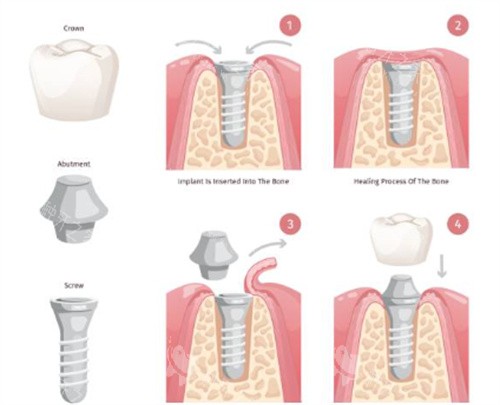

先来说说诺贝尔种植牙,它诞生于1952年,这历史可够悠久的啦!是由“现代种植牙之父”布伦·马克医师发现骨结合理论后研发出来的,在1965年就完成了国内外首例钛种植体临床应用,到现在已经有超过50年的临床验证咯!它有个核心的专有技术,叫“钛易耐TiUnite”表面处理技术,这个技术能模拟骨细胞生长环境,让骨头和种植体更快地结合在一起,对于那些有骨质疏松、糖尿病等复杂情况的患者来说,就很合适呢。

再看看瑞士ITI种植体,它是Straumann集团在1974年推出来的。它可是国内外头一个采用中空柱状结构设计的种植体,有个莫氏锥度连接技术,能减少微动和细菌渗透。临床数据显示,在下颌后牙区单颗修复,5年存留率能高达98.7%呢。而且它还通过钛锆合金(Roxolid系列)把机械强度提升了40%,特别适合骨量不足的患者。

在技术差异方面,诺贝尔种植体用的是四级冷作钛材质,强度跟五级钛差不多,螺纹设计能让植入的时候扭矩更稳定。而ITI的SLActive亲水表面技术可严峻啦,能把骨愈合时间从原来的6 - 8周缩短到3 - 4周,比传统种植体提速50%呢!像诺贝尔Active型号采用倒锥形冠部设计,能在保留皮质骨的同时实现小创口植入;ITI也有自己的特点,在骨结合速度上表现出色。

材质工艺与临床寿命

从材质工艺来看,诺贝尔种植体和ITI种植体都用的是四级冷作钛。不过诺贝尔主打TiUnite®阳极氧化处理技术,在表面形成多孔氧化层,能增强初期稳定性,这个技术经过20年临床验证,10年存留率能达到98.2%。ITI则是通过SLActive®亲水表面处理技术,能缩短骨结合时间,尤其适合糖尿病、骨质疏松等骨愈合风险较高的人群。

在临床寿命方面,根据《临床口腔种植研究》期刊数据,ITI种植体在国内外范围内累计植入超2000万颗,10年存留率在97.8% - 99.2%。它研发的骨水平种植体(BL/BLT)通过平台转移设计,能把牙槽嵴边缘骨吸收量控制在0.45mm以内,降低了美学区牙龈萎缩的风险。诺贝尔种植体以Active®系列为代表,它的锥形主体与自攻切削螺纹设计,在软骨质中初期稳定性能提升30%。一项覆盖1200例患者的长期追踪显示,其20年存留率仍达95.6%,在即刻种植领域优势明显。